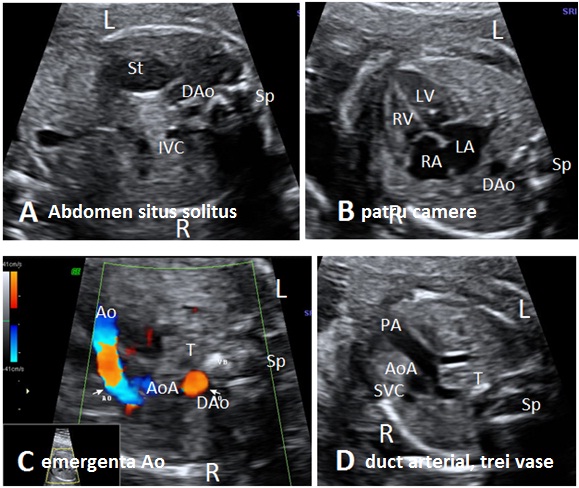

Anomaly: Arc aortic drept + Arc ductal la dreapta (Right aortic arch + patent right ductus) date: 2011-05-15

Aorta descendenta situata intratoracic la dreapta, arc aortic si duct arterial orientate la traheei. Morfologie normala a cordului, aspecte normale Doppler Color (imagini atasate).

Ecocardiografia trim. 2 confirma diagnosticul.